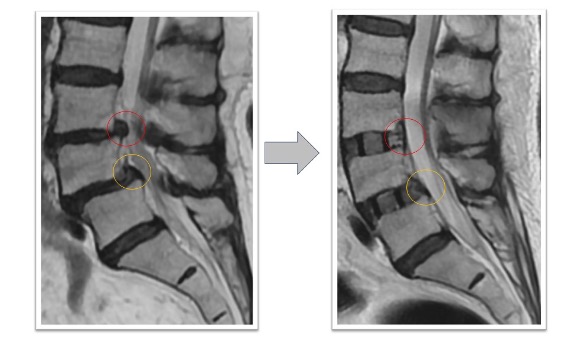

腰椎すべり症+椎間板ヘルニア(図2)

下肢痛で来院し歩行困難のため手術となりました。術前認められていたL3/4の椎間板ヘルニアがOLIFによる固定術後消失(赤丸)、またL4/5に認められていた変性すべり症による椎体のずれ、不安定性も術後は元の脊椎の並びに矯正された状態で固定されています(黄丸)。術後は症状消失し、元通り歩行可能となりました。

図2